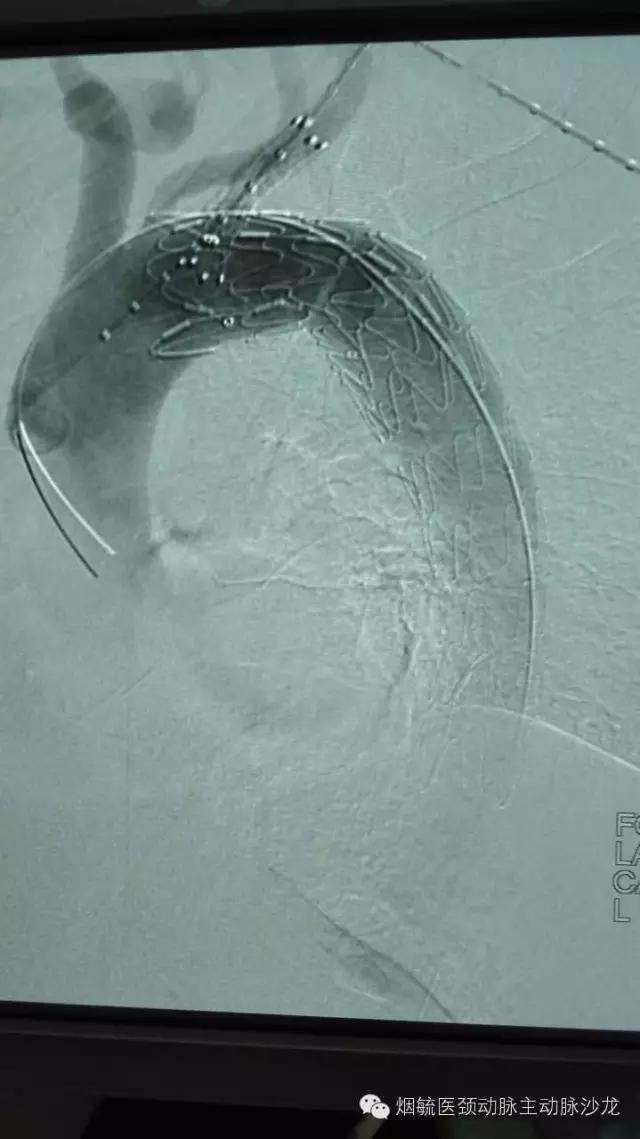

3天前60岁的王大爷前突然胸背部剧烈疼痛,疼到大汗淋漓,只能弯腰或屈膝卧床来缓解疼痛。在外院检查出胸主动脉穿透性溃疡合并璧间血肿,属于濒临破裂穿孔形成假性动脉瘤,必须立即手术,由于外院条件限制,家人带着王大爷来到烟台毓璜顶医院血管外科就诊。接诊的勇俊副主任医师为王大爷进行了紧急控制血压止痛等对症处理,并迅速组织科室专家会诊,讨论病情,制定手术方案,以杨牟教授为首的专家团队一致认为,手术刻不容缓,需紧急处理。在麻醉科及导管室工作人员的配合下,由张居文副主任医师带领的勇俊副主任医师、刘国龙主治医师和王涛住院医师组成血管外科动脉小组当天为患者实施了“胸主动脉腔内隔绝术+左锁骨下动脉烟囱置放手术”,手术顺利,患者转危为安。